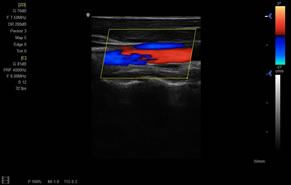

> 彩色血流量圖(CDE)

> 彩色血流分辨增強技術